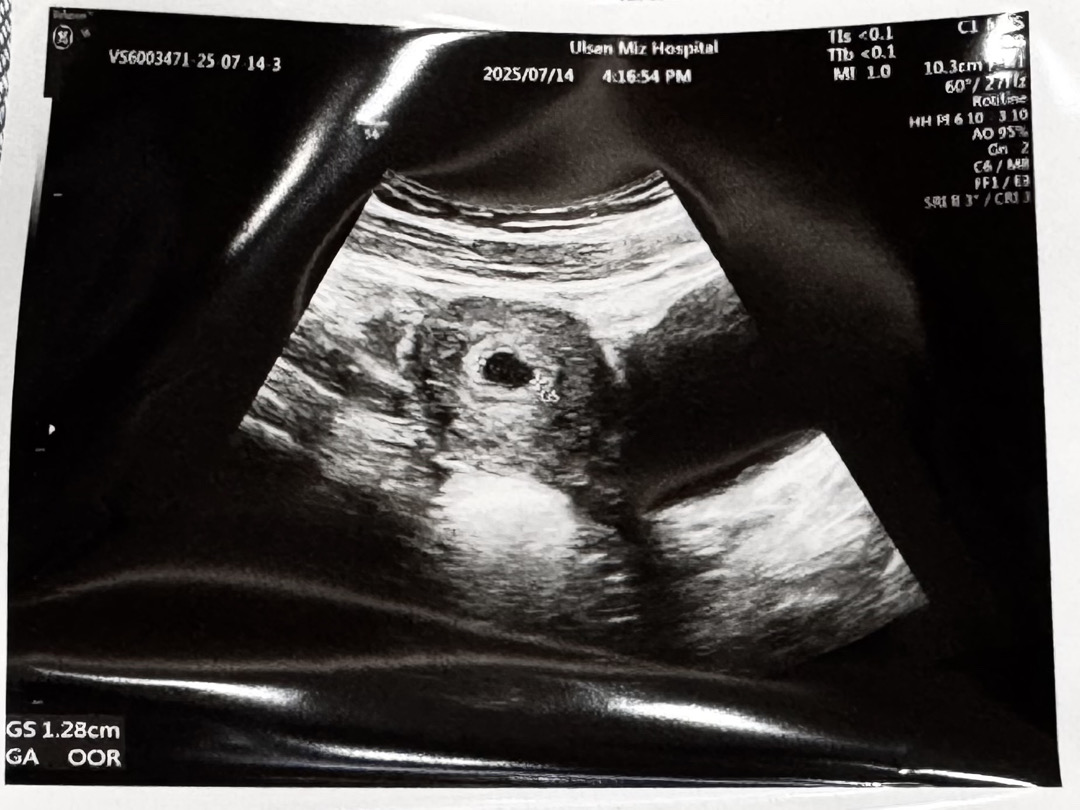

질출혈있어서 걱정됐는데 아기집 잘 확인했어요

생리 시작 할때처럼 투명냉+핏줄기로 시작하더니 1일차 혹은 마지막날 양처럼 피가 냉이랑 섞여나와서 병웠다녀왔어요 타이유 주사도 맞고왔고 마음 편하게 가지려고 노력중이에요. 혹시라도 질출혈때문에 걱정되는 엄마들 있을까봐 글 남겨요! 누구나 어느정도는 선홍색,갈색 피 나올 수 있대요!! 절박유산 정도면 진짜 붉은 새빨간피에요 너무 걱정마세요. 저는 이제 6주 들어가네요. 만출까지 모두 화이팅🤍🤍